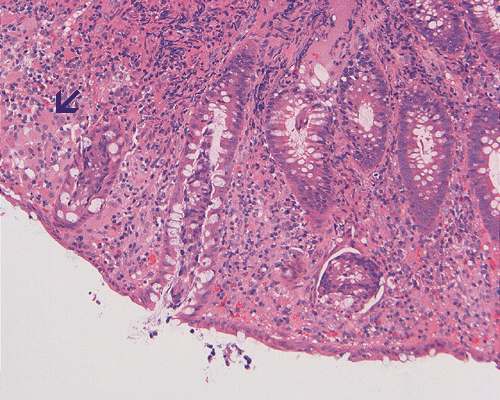

On low-magnification, the biopsy appears to be a piece of colonic mucosa without evidence of necrosis, erosion, or ulcer (Panel A). On medium-magnification, the lamina contains some vaguely formed collections of large cells (Ú in Panel B). On high-magnification, there are many large, round cells with eccentric nuclei. These are macrophages in clusters that are consistent with granulomas.  Many small, grayish to basophilic, vesicle-like structures are present in the cytoplasm (Panel in C). In other areas, these large, round cells do not really form small clusters and are admixed with lymphocytes (Panel D). Again, many small, grayish vesicle-like structures are present in these cells. A grayish to basophilic core is present and is surrounded by halo (Ú in Panel E).  These structures are most suggestive of microorganisms particularly fungus. On periodic acid Schiff (PAS), these vesicles appear bright purple-red (Panel F and G). The basophilic core is also strongly positive for PAS stain (Panel G). These microorganisms appear dark with Gomori methamine silver stain (Panel H and I).

Comment: The pathologic changes in this case are morphologically consistent with histoplasmosis. The patient is immunocomrpomised (HIV-2 positive). Typical to these cases are poorly formed granuloma as illustrated in this case.

DIAGNOSIS: Histoplasmosis (in an HIV seropositive patient) of colon.

In immunocomprised patients that have defective cellular immunity, granuloma formation may be rather indistinct as illustrated in our case. The yeast form of Histoplasma capsulatum is found in tissue and they are usually under 5 mm in diameter and appear as ovoid yeasts.  The lung is the most affected organ. Granuloma formation, typically multiple, with extensive caseous necrosis and a variable amount of calcifications are the typical pathologic changes in the lung. These granulomas are often demarcted from the surrounding tissue by a fibrous wall. Granulomas in the lung can get quite calcified with time. The pulmonary nodules can also enlarge slowly to give a wrongful clinical impression of neoplasm, the so-called histoplasmoma. The living yeast in tissue, often occur in clusters, has a basophilic center and a translucent halo that represents the capsule. They are often engulfed by histiocytes as illustrated in this case. Dead organisms appear eosinophilic and cannot be detected easily in granuloma by hematoxylinj-eosin stain. The microorganism is numerous and can be identified on routine hematoxylin-eosin stain with astute observation and high index of suspicion. Typically, there are numerous yeasts and they are present even in heavily calcified nodules or granulomas.